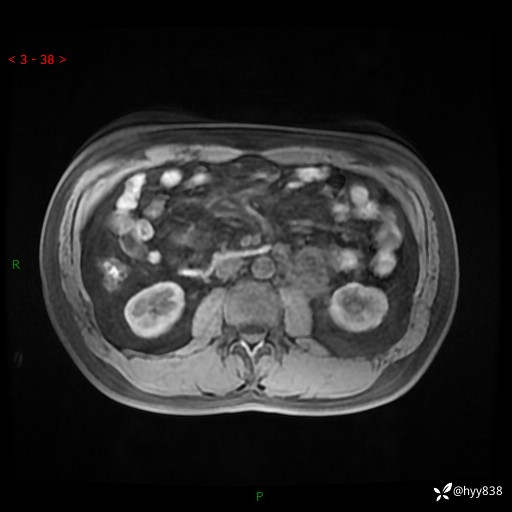

现病史:患者3月余前检查发现左侧腹膜后占位,大小约3.7*4.9cm,平素无腰疼,无肉眼血尿,无尿频尿急等不适,当时未特殊处理,在门诊复查CT提示左侧腹膜后占位,门诊拟“左侧腹膜后占位”收入院。 起病以来,患者精神佳,饮食、睡眠良好,大小便正常,体力体重无明显变化。

MRI增强